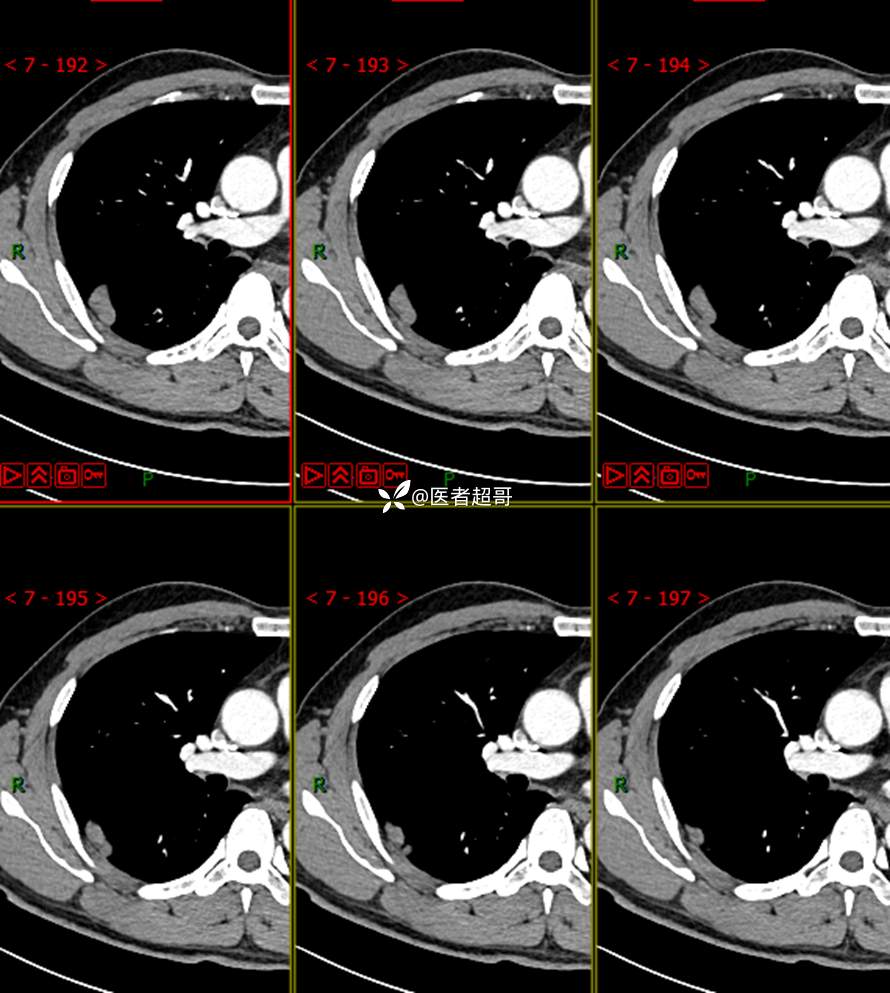

现病史:患者1年余前于体健中心行胸部X片发现右上肺叶密度增高影,无明显咳嗽,咳痰,无痰中带血及咯血,无胸痛及胸闷、气短,无发热、盗汗及全身乏力。无头痛、头晕,无腹痛、腹胀及恶心、呕吐,无声音嘶哑及呛咳,未行特殊治疗。后患者定期复查胸部CT,未见明显变化。2023-2-6患者于我院复查胸部CT:右肺上叶、下叶交接处胸膜下见实性结节影,最大截面约2.6cm×1.4cm,较前增大,建议行手术治疗。今为求进一步诊治,遂来我院就诊,门诊以“肺肿物”收入我院,患者自发病以来,神志清,精神可,饮食可,睡眠良好,大小便正常,近期体重未见明显增减。